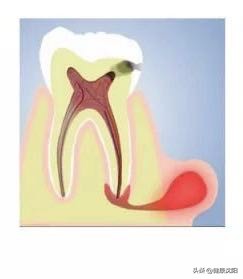

在日常生活中,之所以会出现牙龈上反复长脓包的情况,大多数是因为得了一种叫做“慢性根尖周炎”的牙齿疾病,是牙齿根尖周围组织发炎引起的。分析其原因,很可能是因为龋病、牙外伤、牙髓炎等牙齿问题没有得到及时治疗,或者是既往牙髓治疗不完善,导致牙根根尖周围的牙槽骨慢性进行性破坏。慢性根尖周炎通常没有明显的自觉症状,患者可在咀嚼时有不适感,通常是以牙龈脓包为主诉就诊。因为在日常生活中,大家经常以“牙痛”来衡量牙齿是否有问题,如果牙齿不出现疼痛,大家就以为牙齿没有问题了,或者认为牙痛好了。其实坏死的牙髓里的细菌仍然在繁殖,炎症通过根管及根尖端慢慢向牙槽骨里蔓延。长此以往牙龈上就长了脓包。

那是因为慢性根尖周炎的病变过程并不是单一的骨破坏过程,而是一个破坏与修复双向进行的病例变化,当身体抵抗力强时,脓包就会消退,当身体抵抗力弱时,脓包又会出现,这样反反复复出现。

如果不进行根管治疗及消炎等措施,可能会出现炎症感染扩散及临近颌骨出现吸收破坏的情况,造成临近牙齿的逆行性感染。